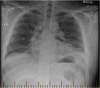

An esophagopericardial fistula developed in a 33-year-old patient after radiofrequency ablation for atrial fibrillation. He was initially managed with an esophageal repair and a left atrial bovine pericardial patch and eventually an esophagectomy. At 6-month follow up he had no symptoms. The case highlights the complexities of managing this life-threatening complication. (Level of Difficulty: Advanced.).